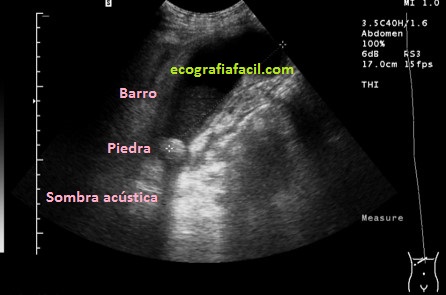

Finalmente, la imagen 4, donde encontramos una vesícula sin barro biliar y con una gran colelitiasis que provoca una evidente sombra acústica posterior. La vesícula es anecoica, sin presencia de barro, el paciente puede ser completamente asintomático y no saber que esa ecoestructura, redondeada, hiperecogénica causante de sombra acústica posterior y móvil, que así suelen ser las colelitiasis, se alberga en el interior de su vesícula. Las colelitiasis suelen ser variable en número, tamaño e incluso forma.

En ocasiones, barro y piedras, pueden coexistir en el contexto de patologías en esta región. Puedes verlo en la imagen 5 con la semiología ya descrita anterioremnte.